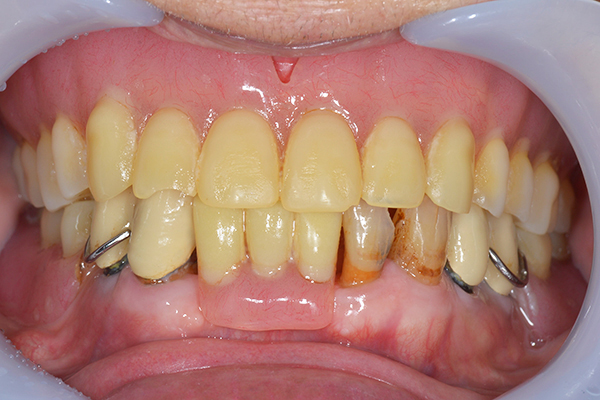

完成した入れ歯とかぶせ物です。 入れ歯への寛容度が高い患者様でしたので、 金属は使用せず、プラスチックのみで上は仕上げました。 下顎も歯は1本減ってしまいましたが、しっかり 入れ歯が維持できる様な構造にしました。

お口の中に入れた状態です。 見た目も最初とほとんど変わることなく作成できました。 維持や吸着に関しても問題ないようでした。